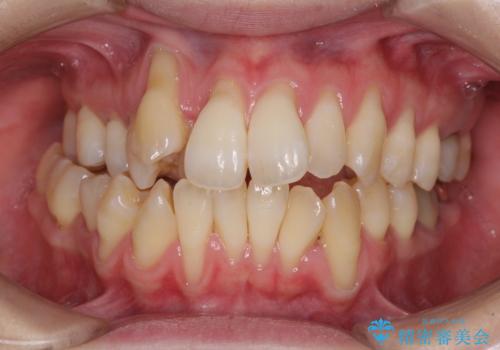

前歯のでこぼこをスッキリと 目立たない装置による抜歯矯正

- 前歯のでこぼこを気にして来院された患者様です。

でこぼこの解消とともに、やや閉じにくそうな口元を引っ込めることを目的とし、上下左右の第一小臼歯4歯を抜歯をしてワイヤー矯正により治療することとしました。